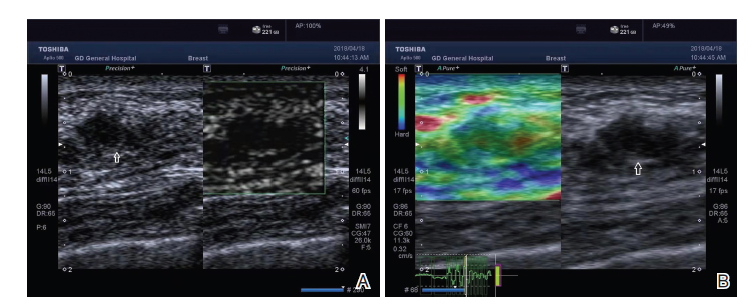

图1 乳腺腺病mSMI及RTE表现

注:女性, 52岁。右侧乳腺发现低回声结节(箭头所指)最大直径约13 mm、实性、低回声, 边界不清, 边缘模糊, 形态不规则, 纵横比< 1, 内部无钙化, 常规超声评估为恶性结节, ACR BI-RADS 4类。A. mSMI表现为Ⅰ 型; B. RTE 1分, 多模态式超声检查评估为良性结节, 经手术病理被证实为乳腺腺病

Fig.1 mSMI and RTE manifestations of breast adenosis

Note: Female, 52 years old. A hypoechoic nodule (indicated by arrow) with a maximum diameter of about 13mm was found in the right breast. It was solid, hypoechoic, with unclear boundaries, blurred edges, irregular shape, aspect ratio < 1, and no calcification inside. It was assessed as a malignant nodule by conventional ultrasound, ACR BI-RADS type 4. A. mSMI presents as typeⅠ ; B. RTE was 1 point, benign nodules were evaluated by multimodal ultrasound, it was proved to be mammary gland adenosis aftersurgery and pathology